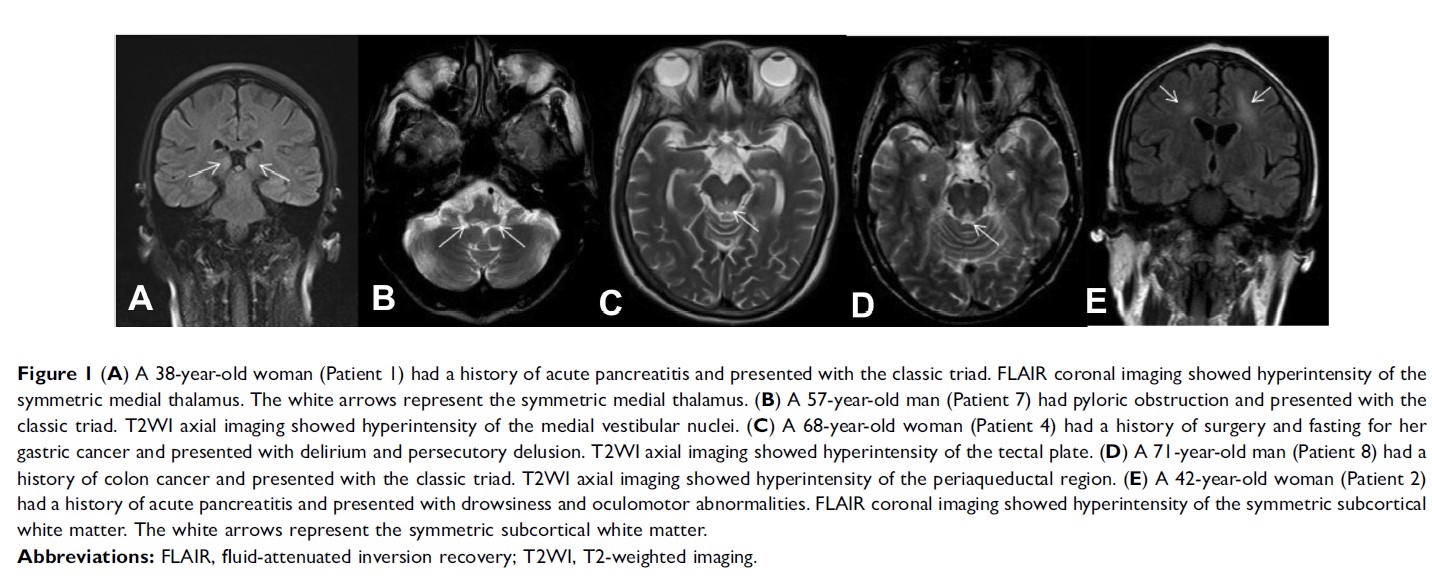

9 例非酒精性韦尼克脑病患者的临床特征和磁共振成像:一项回顾性研究